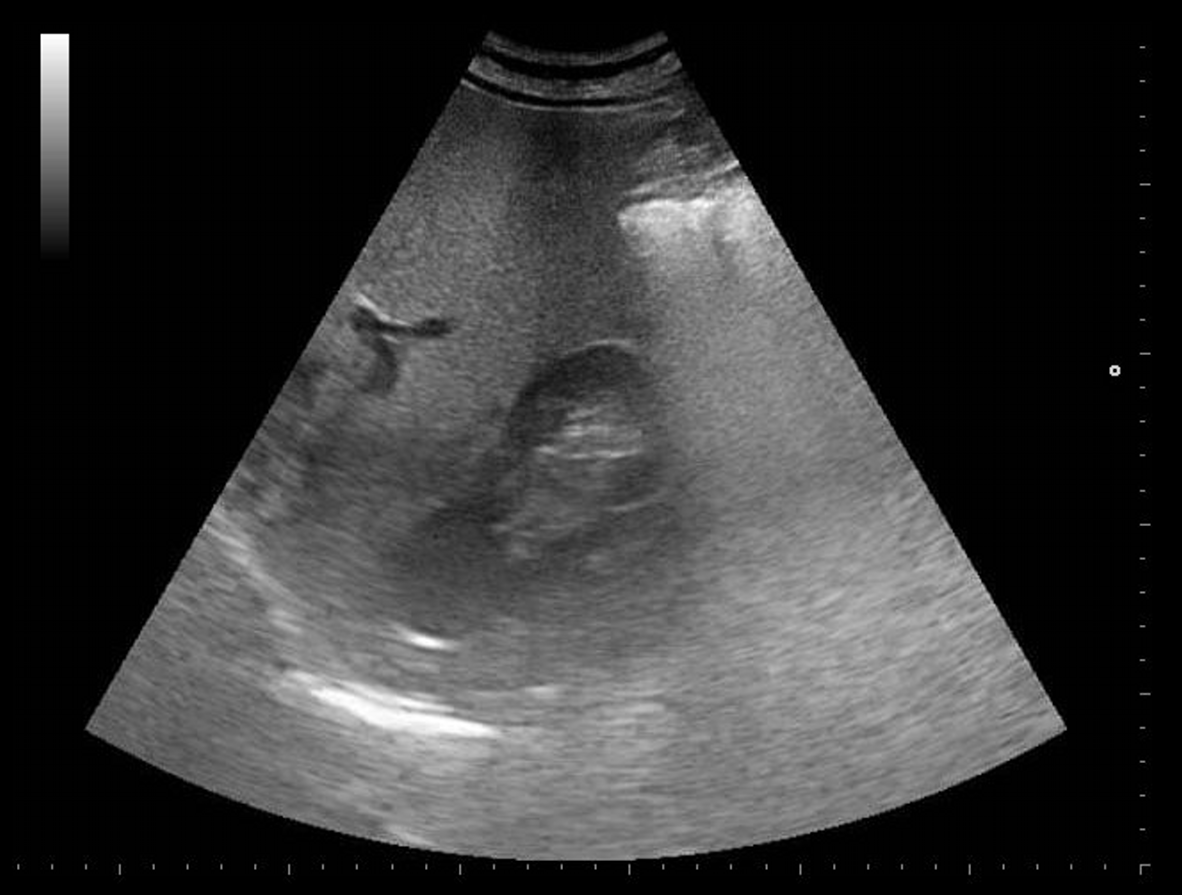

Paciente de 64 años que consulta por dolor en hipocondrio derecho de varias semanas de evolución. Se le realiza ecografía en su centro de salud donde se detecta imagen quística de 3 cm aproximadamente en riñón derecho. Se solicita TAC de abdomen para estudio de patología biliar que no se realiza por deseo del paciente.

Ecografía abdominal con vesícula biliar de paredes lisas sin imágenes en su interior, riñones simétricos con quiste renal de unos 3 cm en polo superior de riñón izquierdo sin otras lesiones o alteraciones visibles. Exploración limitada por abundante gas intestinal.

A las pocas semanas, el paciente consulta a Urgencias por hematuria macroscópica donde se le realiza una TAC y se observa masa renal izquierda dependiente de polo superior sugestiva de carcinoma renal con infiltración de ramas venosas y metástasis adrenal derecha.

Dado que fue un hallazgo accidental en un estudio de posible colelitiasis, de difícil valoración por ecografía, se solicitó TC abdominal para ampliar el estudio y poder definir bien sus características. Aparición de nueva sintomatología, hematuria, que reorienta el diagnóstico a patología renal.

Después de hallazgo ecográfico y nueva sintomatología. Se confirma por TC el hallazgo de masa renal izquierda con metástasis adrenal fue valorado por Urología y se realizó nefrectomía radical izquierda con suprarrenalactomía derecha.